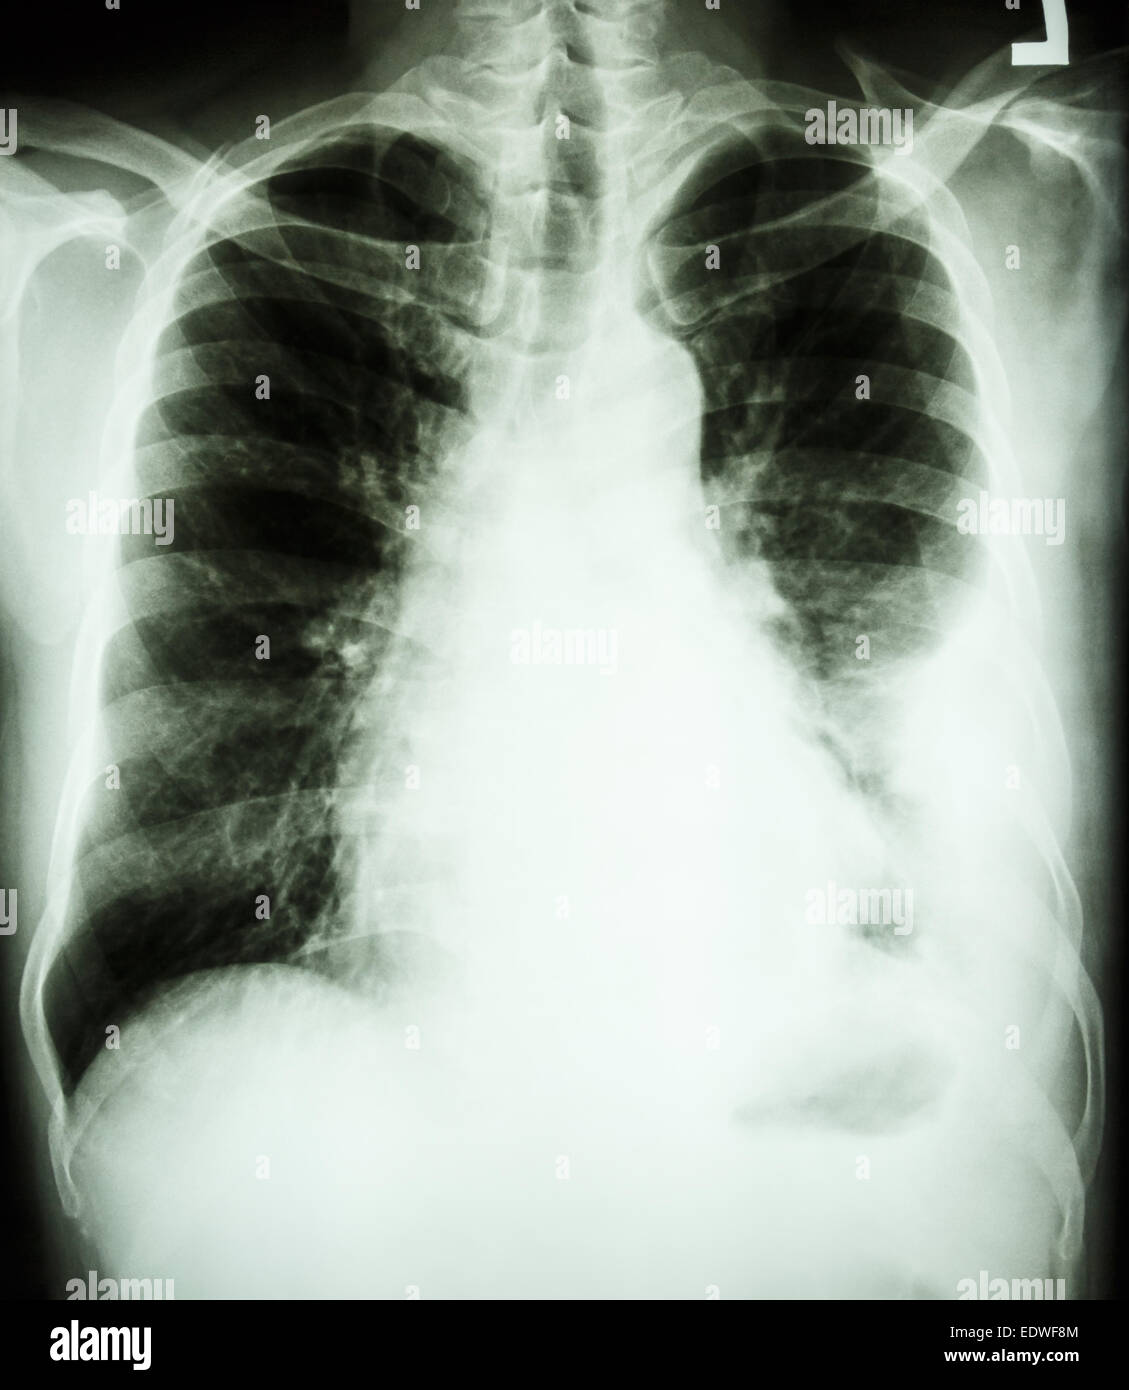

Raio X De Derrame Pleural

Webo derrame pleural é o acúmulo excessivo de líquido no espaço pleural, sendo normalmente uma complicação que surge devido a problemas como pneumonia,. Webas principais causas de derrame pleural são: Tuberculose (geralmente é unilateral. Webla homeostasia resultante deja 5 a 15 ml de líquido en el espacio pleural normal. Un derrame pleural es una acumulación anormal de líquido en el espacio pleural. Webpronto, suspeitei de um derrame pleural no meu exame físico, agora só preciso confirmar. O jeito mais simples de fazer isso é solicitando um raio x de tórax, um exame simples,. O diagnóstico é feito com. Webo derrame pleural é o acúmulo anormal de líquido no espaço pleural (o espaço entre as duas camadas da membrana fina que reveste os pulmões). O líquido pode se acumular.

Weba american thoracic society classifica a reação pleural como um processo infeccioso em três fases anatomopatológicas consecutivas; Fase aguda ou exsudativa, inicial,. Websaiba o que é derrame pleural, como é feito o exame de radiografia do tórax em posição lateral e quais são as vantagens e desvantagens desse método. Webum derrame pleural acontece quando líquido se acumula entre as superfícies pleurais parietal e visceral do tórax. Uma camada fina de líquido está. Weba radiografia em decúbito lateral com raios horizontais (fig. 1) é mais sensível do que a em posição ortostática para o diagnóstico de derrame pleural e pode demonstrar coleção. Webapós idas e vindas ao hospital regional de aquidauana, distante 41 quilômetros de campo grande, somente na terceira consulta os pais de uma criança de. De forma geral, precisa. Webessa semana no portal da pebmed falamos sobre orientações para o manejo de pacientes com derrame pleural.

Por isso, em nossa publicação semanal de. Contudo, em casos de doenças que afetam a pleura, pode haver acúmulo de líquido nesse espaço, dando origem ao derrame pleural. Webem geral, a radiografia na incidência posteroanterior é capaz de detectar derrames pleurais a partir de 200ml, enquanto a incidência em perfil é mais sensível e detecta derrames. Se esse conteúdo foi útil para você, curta a publicação para que ela alcance mais colegas.